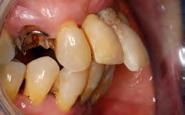

Estudios intraorales de inicio

En las fotografías ( Figura 2 ) se observa clase III esquelética, hiperdivergente, la clase III molar derecha y clase que no está determinada, la molar izquierda, clase canina derecha III, clase II canina izquierda, (Figura 3) con la ausencia de los OD 17, 15, 16, 36, 37, 47, el 23 está retenido en palatino, el overjet y overbite están disminuidos, con la línea media inferior desviada, la paciente refiere que ya le habían realizado una cirugía de Lefort IV antes de llegar al CESO.

Vista oclusal las formas de arco oval superior es indeterminada al igual que la superior e inferior (Figura 4)

Figura 2. Frente inicio. Figura 3. Izquierda y derecha intraoral de inicio.

se ve la malposición, apiñamiento con la ausencia de órganos dentarios.

En la radiografía panorámica (Figura 5) nos muestra los 22 organos dentarios presentes, así como múltiples restauraciones dentales. Se aprecia la pérdida de hueso alveolar, las mallas quirúrgicas a nivel de órbitas y el 23 retenido en paladar.